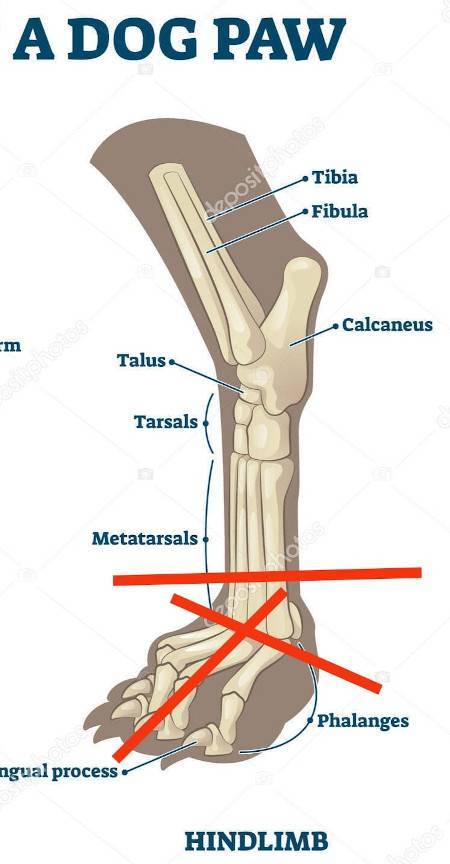

Ellie ist ca. 1 Jahr alt (Stand 08/2024) und hat bereits eine bewegte Vergangenheit hinter sich. Nach 5 Tagen intensiver Versuche konnte sie endlich von der Strasse gerettet werden, wo sie hungrig, durstig und in einem schlechten gesundheitlichen Zustand allein und orientierungslos umherirrte. Elli war von Flöhen und Zecken geplagt und stark abgemagert, doch trotz all dieser Herausforderungen zeigt sie einen unglaublichen Lebenswillen. Elli hat ein Handicap: Ihr fehlt ein Fuß am Hinterbein. Ob dies auf einen Unfall oder eine angeborene Fehlbildung zurückzuführen ist, wissen wir nicht. Doch Elli lässt sich davon nicht einschränken! Sie zeigt sich flink und steckt voller Energie. Ellie kommt erstaunlich gut mit ihrem Bein zurecht, es stört sie in keiner Weise und sie kann problemlos laufen, spielen und sogar rennen. Dennoch benötigt sie einen Schutz für ihren Stummel, entweder eine passende Prothese oder einen gefütterten Silikonschuh. Dies sollte in ihrem neuen Zuhause gründlich tierärztlich abgeklärt werden. Trotz ihrer Vergangenheit ist Elli eine unglaublich liebe, verschmuste und fröhliche Hündin. Sie liebt die Nähe zu Menschen, ist sehr anhänglich und versteht sich gut mit anderen Hunden. Ihre neuen Menschen sollten Freude daran haben, ihr alles ruhig und geduldig beizubringen, was so ein junges Mädel für ihr weiteres Leben als Familienhündin wissen muss. Ebenso sollten sich die neuen Besitzer bewusst sein, dass ein Hund nicht nur Freude, sondern auch jede Menge Arbeit und Verantwortung mit sich bringt, damit Ellie sich zu einer tollen Begleiterin entwickeln kann. Für unsere Herzensbrecherin suchen wir ein liebevolles, fürsorgliches und dauerhaftes Zuhause, wo sie nebst viel Spass auch abwechslungsreiche Spaziergänge erleben darf, wo sie artgerecht ausgelastet wird und täglich die Zuwendung und Pflege bekommt die sie verdient. Wer erfüllt den Traum von unserer Zuckerschnute Ellie und gibt ihr trotz ihres kleinen Handicaps die Chance ein treues Familienmitglied zu werden?